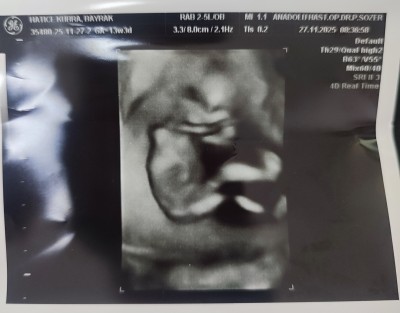

11 haftalık ve 13+5 haftalık ultrason görüntülerimiz doktor cinsiyette emin olamadi önce erkek sonra kız dedi ama sizin tahminleriniz neler?

Gebelik haftası 13+5